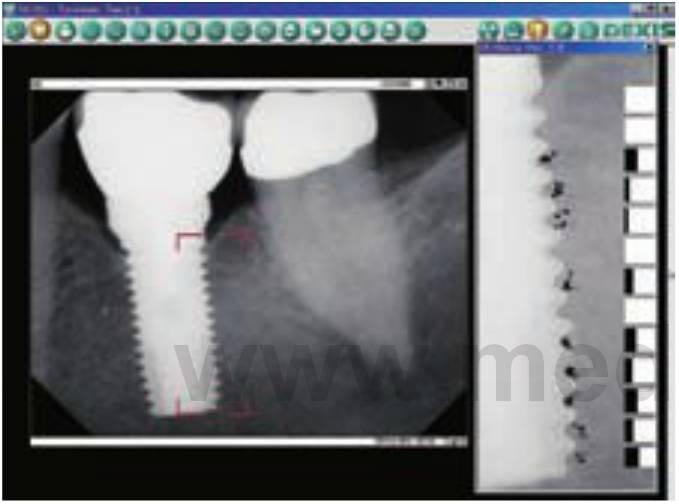

Uno de los adelantos recientes más significativos en la radiología dental ha sido la introducción de la tecnología digital que ha permitido reducir numerosas limitaciones de la radiografía intraoral convencional. Las ventajas de la radiografía digital y sus usos en la implantología oral están bien documentadas. Con el empleo de la radiografía digital, los procedimientos quirúrgicos implantológicos y las prótesis se han simplificado con un aumento de la eficiencia.

La radiología digital es un procedimiento de imagen en el cual la película es sustituida por un sensor que recoge los datos. La información analógica recibida es interpretada por un programa especializado, y se formula una imagen en la pantalla del ordenador. La imagen resultante puede ser modificada de diferentes maneras, como con la escala de grises, el brillo, el contraste, y la inversión. Se pueden formar imágenes en color para ampliar la imagen digital para una mejor evaluación. Actualmente están disponibles programas informáticos (ej. Dexislmplant) que permiten la calibración de imágenes magnificadas, además de asegurar mediciones exactas (fig. 3-2).

Al compararlos con las radiografías convencionales, los sistemas digitales más actuales tienen una significativa menor radiación con una resolución superior. En cualquier caso, con respecto a la implantología oral, la ventaja más significativa de la radiografía digital es la velocidad instantánea a la cual se forman las imágenes que es altamente útil durante la colocación quirúrgica de los implantes y la verificación de la colocación de los componentes protésicos (fig. 3-3).